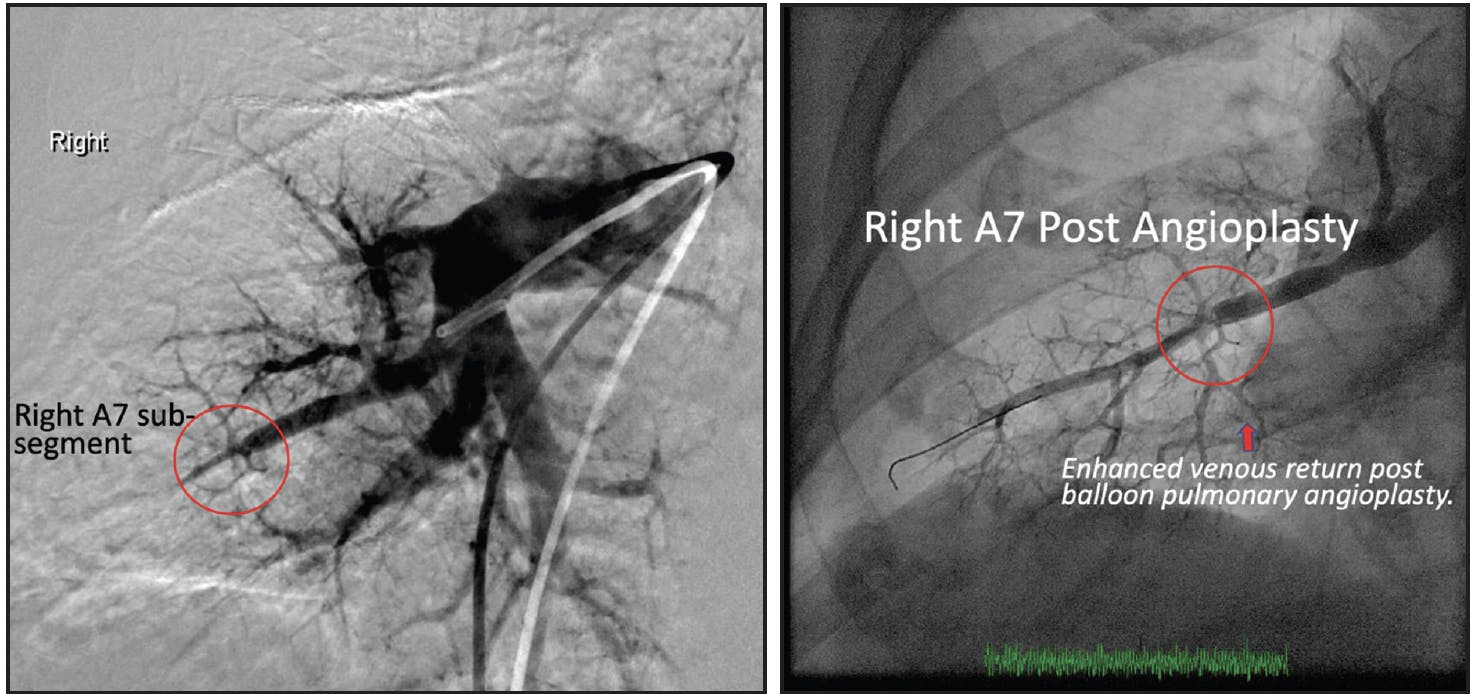

Treatment extended to right segments A7, A9, and A10. Cannulation employed a JR4 guide catheter. A7 and A10 segments showed intravascular webbing, addressed similarly to right A4 in the previous session. The A9 segment presented with a total occlusion at the distal segmental branch level. Initial lesion crossing involved a Sion blue guidewire with a supporting 0.014-inch crossing catheter, followed by the use of an undersized 2-mm balloon for dilatation, considering the high risk of reperfusion edema with total occlusions (Figure 2).

Figure 2. Successful BPA of the right A7 subsegment.